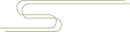

这是一例三踝骨折的患者。